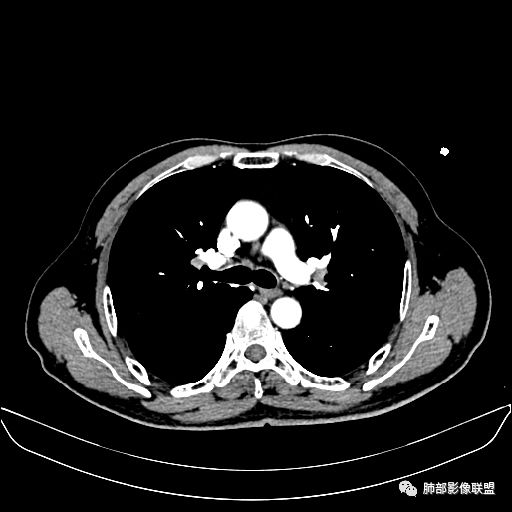

入院CT

老年男性,因“咳嗽咳痰1月余。”入院。病程中咳嗽咳痰,咳黄白痰,间断咯少许鲜红色痰血。PPD阳性。胸CT:右肺中叶外侧段支气管管腔阻塞,大片实性病变,病灶边缘光滑,部分边缘膨隆,可见分叶,肺门及纵隔可见肿大淋巴结,并可见钙化。增强可见病灶明显强化,而且延迟强化明显,病灶内多发低密度区,内见血管影,血管变细、部分血管破坏。考虑恶性病变可能性大,鉴别慢性肉芽肿性病变。

老年男性,咳嗽、咳痰1月余,间断血痰。PPD阳性。

胸CT:跨叶大肿块,主体在中叶,右中叶外侧段支气管阻塞,病灶部分边缘膨隆,可见分叶,部分边缘平直,肺门及纵隔可见肿大淋巴结。增强病灶不均匀强化,延迟强化明显,病灶内多发低密度区,内见血管飘浮,部分血管变细、模糊。考虑:恶性病变可能性大,大细胞?淋巴瘤?鉴别慢性肉芽肿性病变。